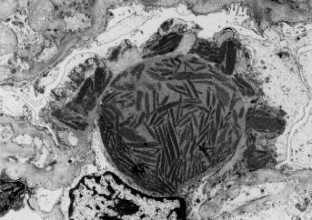

Die Lupusnephritis ist ein bekanntes Phänomen beim systemischen Lupus erythematodes (SLE). Wir untersuchten die Nierenbiopsie einer 30-jährigen Frau mit SLE. Die Anamnese zeigte einen klinisch typischen SLE mit generalisierten Symptomen mit positivem ANA- und Anti-ds-DNA-Titer ohne Nachweis von Lupuskoagulans, des Rheumafaktors, von Kryoglobulinen sowie ohne Antiphospholipid-Antikörper. Eine Paraproteinämie war weder für IgG noch für IgA oder IgM nachzuweisen. Mit Hilfe der Lichtmikroskopie, der Elektronenmikroskopie sowie der Immunelektronenmikroskopie wurden elektronendichte Ablagerungen in subepithelialer, subendothelialer und mesangialer Lokalisation nachgewiesen. Zusätzlich fanden wir sowohl in den elektronendichten Ablagerungen, als auch im angrenzenden Mesangium Kristalle eines elektronendichten Materials. Diese kristallinen Strukturen sind aus IgG und κ-Leichtketten zusammengesetzt, während IgM, IgA sowie λ-Leichtketten mittels Immunelektronenmikroskopie nicht nachzuweisen waren.

Lupus nephritis is a common phenomenon in Systemic Lupus Erythematosus (SLE). We analyzed a renal biopsy of a 30-year-old woman with SLE. The clinical history showed a typical SLE with generalized symptoms without demonstrable lupus coagulant, positive for anti-nuclear antibodies and anti-ds-DNA antibodies but negative for rheumatoid factor, cryoglobulins and antiphospholipid antibodies. A paraproteinemia for IgA, IgG and IgM was not detectable. Using light, electron and immunoelectron microscopy electron-dense deposits were noted in subepithelial, subendothelial and mesangial position. Most remarkably, the electron-dense deposits and mesangial areas in the vicinity of deposits contained an electron-dense crystalline material. The crystalline structures were composed of IgG and kappa light chains, while they were negative for IgM, IgA and lambda light chains, as demonstrated by immunoelectron microscopy.

Abb. 1.